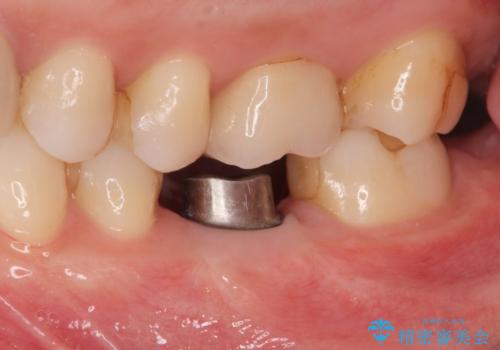

欠損部のインプラント補綴

- 失った奥歯にインプラント治療を受けたい、と希望され来院されました。

前後の歯を削らずに機能回復できるインプラントを用いて審美生、咬合機能の回復を計画します。

- 44万円(インプラント・チタンカスタムアバットメント・ジルコニアクラウン・仮歯)費用は治療当時の料金となります

痛みや腫れもほとんどなくインプラント治療を終えられ、しっかり噛むことができるようになった。と治療結果に満足いただくことができました。